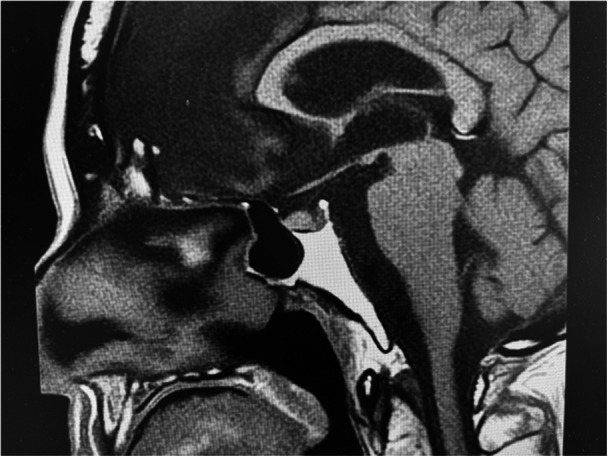

Case presentation: The patient was a 73-year-old man with bipolar disorder Type I. His psychiatric symptoms had been stable for many years. However, polyuria and weakness began to appear at the age of 73. Initially, lithium-induced NDI was suspected, but in the end, partial CDI was suspected because urinary osmolality did not exceed 300 mOsm/L even after water restriction, and administration of nasal arginine vasopressin solution partially increased urinary osmolality.